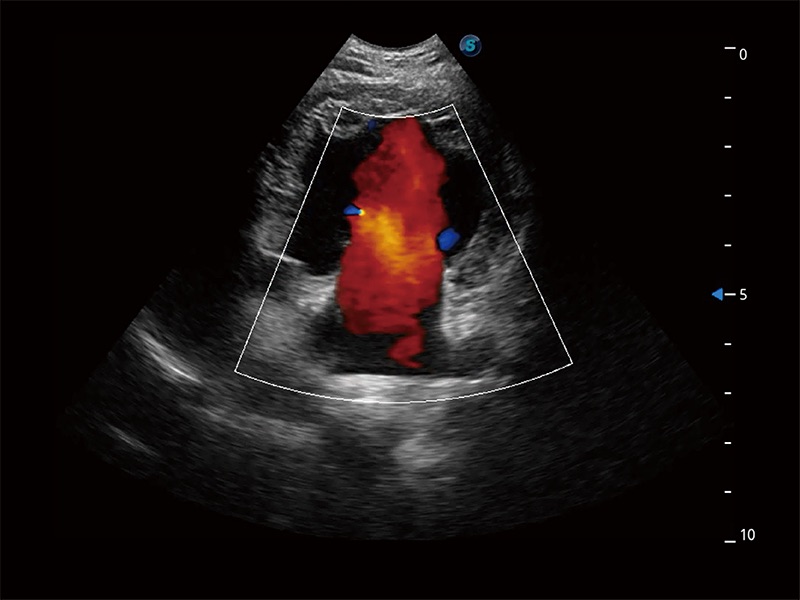

(犬)四腔心MQA

• MQA 心肌定量分析

通过心肌识别技术与二维斑点追踪技术相结合,对心脏的超声图像进行量化分析。计算心肌17个节段的应变、应变率、速度、位移等,并通过牛眼图的形式进行呈现。